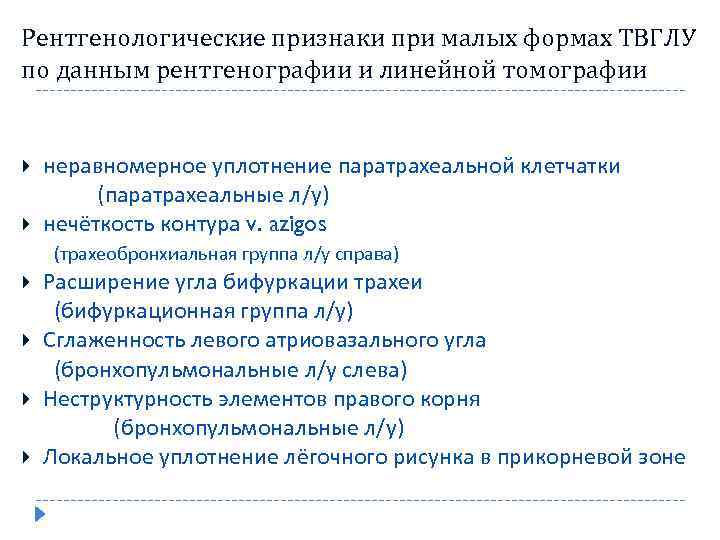

Рентгенологические признаки при малых формах ТВГЛУ по данным рентгенографии и линейной томографии неравномерное уплотнение паратрахеальной клетчатки (паратрахеальные л/у) нечёткость контура v. azigos (трахеобронхиальная группа л/у справа) Расширение угла бифуркации трахеи (бифуркационная группа л/у) Сглаженность левого атриовазального угла (бронхопульмональные л/у слева) Неструктурность элементов правого корня (бронхопульмональные л/у) Локальное уплотнение лёгочного рисунка в прикорневой зоне

Рентгенологические признаки при малых формах ТВГЛУ по данным рентгенографии и линейной томографии неравномерное уплотнение паратрахеальной клетчатки (паратрахеальные л/у) нечёткость контура v. azigos (трахеобронхиальная группа л/у справа) Расширение угла бифуркации трахеи (бифуркационная группа л/у) Сглаженность левого атриовазального угла (бронхопульмональные л/у слева) Неструктурность элементов правого корня (бронхопульмональные л/у) Локальное уплотнение лёгочного рисунка в прикорневой зоне